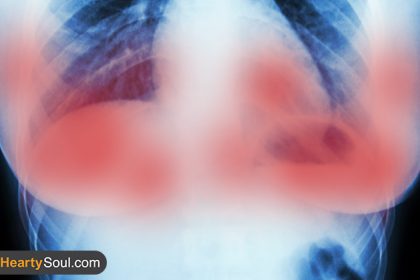

Scientists in Amsterdam destroyed breast cancer tumors in 11 days without chemo : The Hearty Soul

Editor’s Note: This article was originally published September 16, 2016, and has…